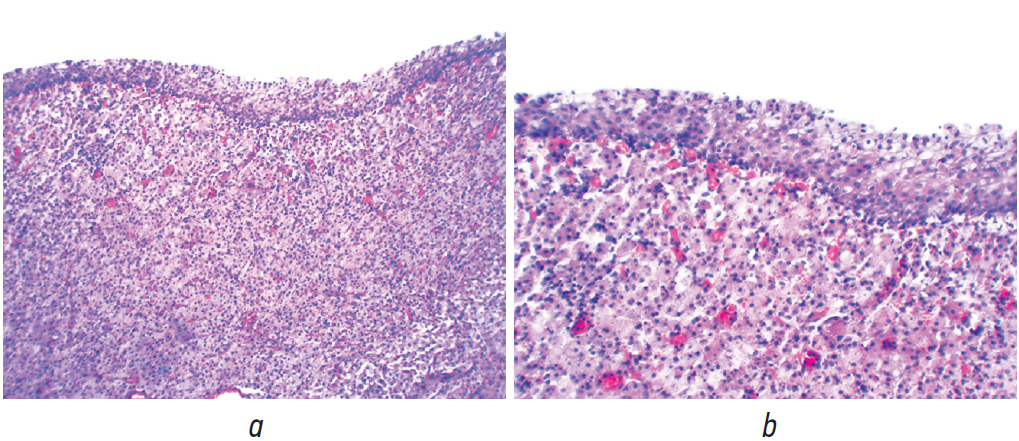

Ранний послеоперационный период протекал без осложнений. Уретральный катетер удален на первые сутки после операции. По результатам гистологического исследования во всех образцах ткани мочевого пузыря, доставленных на исследование, выявлены схожие патоморфологические изменения: в слизистой оболочке диффузно-очаговая инфильтрация крупными клетками типа гистиоцитов округлой, овальной и полигональной формы с пузырьковидными, центрально расположенными ядрами и пенистой цитоплазмой (клетки Ханземанна), с примесью немногочисленных лимфоцитов и гигантских многоядерных клеток. В цитоплазме клеток Ханземанна определяются внутриклеточные базофильные включения (тельца Михаэлиса – Гутмана), которые дают положительную реакцию PAS (Periodic Acid Schiff) при окраске реактивом Шиффа. Со стороны переходного эпителия слизистой оболочки отмечается от умеренной до выраженной атрофия. В целом описанная картина характерна для псевдоопухолевого процесса в слизистой оболочке, редкой формы хронического гранулематозного воспаления — малакоплакии мочевого пузыря. Злокачественного опухолевого роста не выявлено (рис. 4, 5).

Рис. 4. Гистологическая картина малакоплакии мочевого пузыря. Клетки Ханземанна с тельцами Михаэлиса – Гутмана. Окраска гематоксилином и эозином. Увел. ×200 (а), ×400 (b)

Fig. 4. Histological pattern of the malacoplakia of the bladder. Hansemann cells with Michaelis–Gutman bodies. Staining with hematoxylin and eosin. Magnification ×200 (а), ×400 (b)